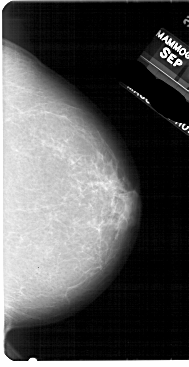

A_1948_1.RIGHT_CC

RIGHT_CC LINES 5491 PIXELS_PER_LINE 2821 BITS_PER_PIXEL 12 RESOLUTION 43.5 NON_OVERLAY